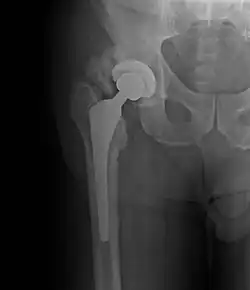

| Heterotopic ossification around the hip joint in a patient who has undergone hip arthroplasty |

Heterotopic ossification of varying severity can be caused by surgery or trauma to the hips and legs. About every third patient who has total hip arthroplasty (joint replacement) or a severe fracture of the long bones of the lower leg will develop heterotopic ossification, but is uncommonly symptomatic. Between 50% and 90% of patients who developed heterotopic ossification following a previous hip arthroplasty will develop additional heterotopic ossification.

Heterotopic ossification often develops in patients with traumatic brain or spinal cord injuries, other severe neurologic disorders or severe burns, most commonly around the hips. The mechanism is unknown. This may account for the clinical impression that traumatic brain injuries cause accelerated fracture healing.[2]

Certain antiinflammatory agents, such as indomethacin, ibuprofen and aspirin, have shown some effect in preventing recurrence of heterotopic ossification after total hip replacement. [7]